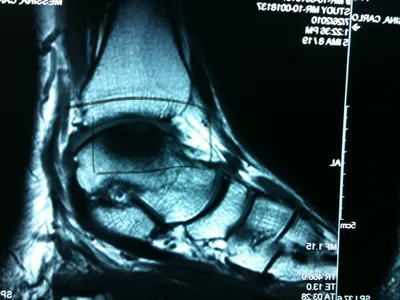

A series of intraop ankle arthroscopy pics of synovial chondromatosis with OCD talus and tibia and microfracture.

Pic of one of the nodules inside the ankle joint.